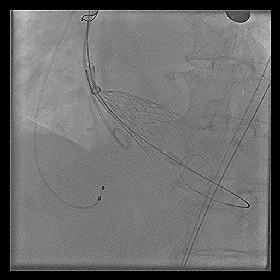

◆2015年1月17日行TAVI术。

◆植入29mm CoreValve人工支架瓣膜一枚。

术后症状明显缓解,近一年未因心衰住院;

一年期复查心超,未见主动脉瓣狭窄和关闭不全。